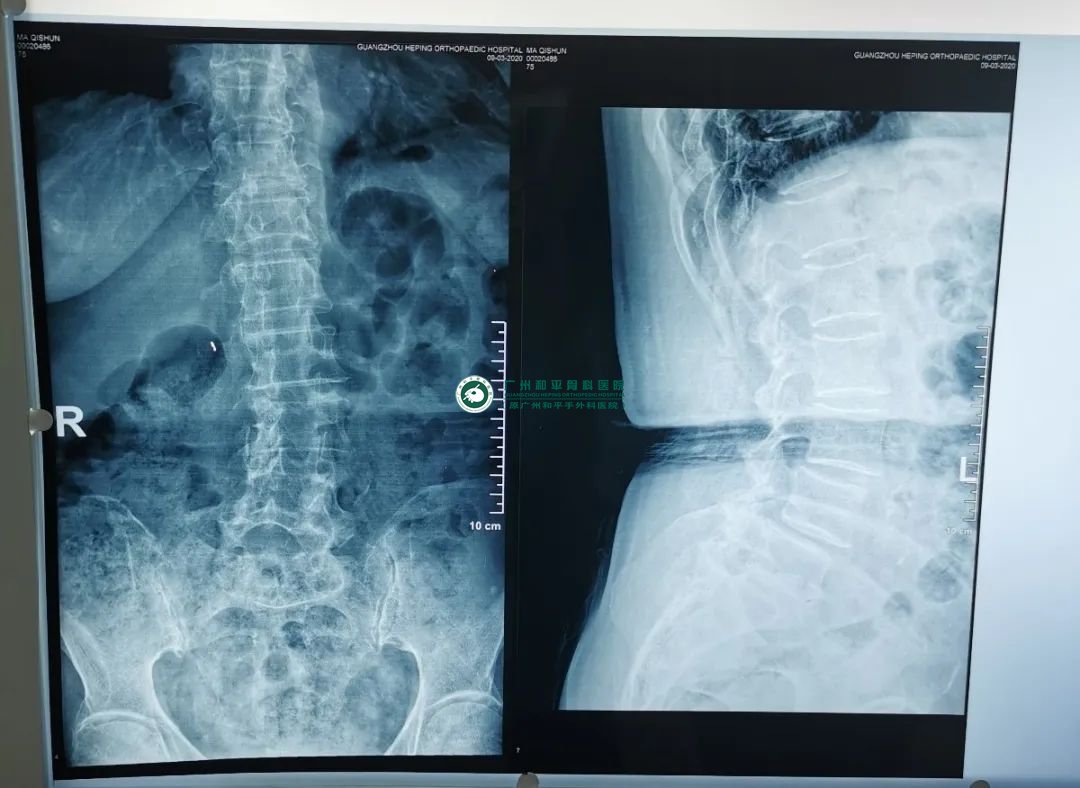

术前:重度骨质疏松症并胸12、腰1椎体压缩性骨折

创伤显微手外科一区晏桂明主任表示,李奶奶患有重度骨质疏松症和胸12、腰1椎体压缩性骨折,加上之前患有多年的骨性关节病,导致了她全身疼痛、活动受限,需要行“手法复位、经皮穿刺、胸12腰1椎体成形术”。李奶奶跟医生说:“这个病真的让我生不如死啊”,听医生说可以手术治疗她的病痛后瞬间感觉有了希望,家人也都对这次手术寄予很大期望,希望手术能减少她的病痛让她轻轻松松地安享晚年。